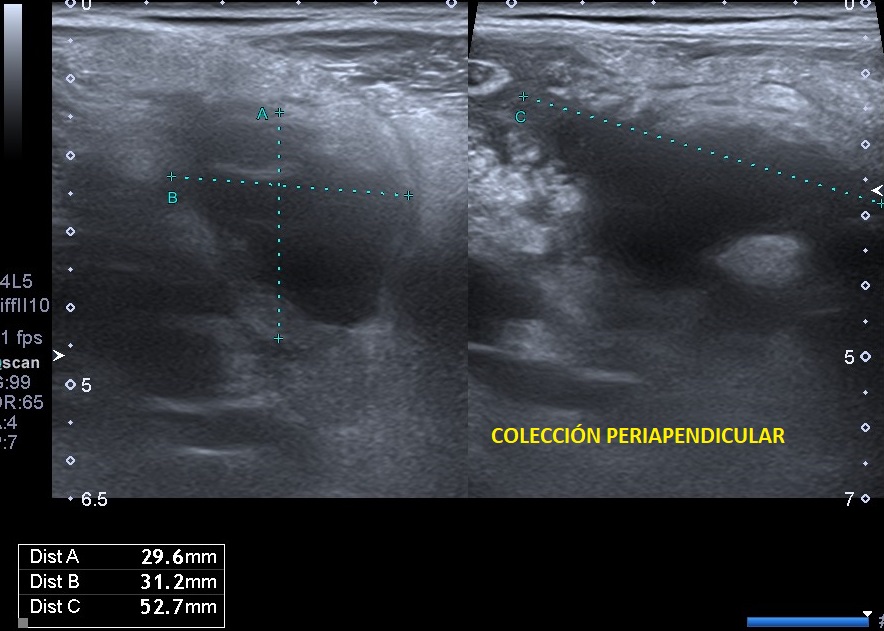

Se realiza una exploración abdominal ecográfica donde se observa hígado de ecogenicidad normal sin lesiones ocupantes de espacio. Vesícula biliar normal, vía biliar no dilatada. Ambos riñones de tamaño y aspecto normales. Páncreas, bazo y aorta normales. En fosa ilíaca derecha se observa apéndice cecal engrosado (imagen 1) con llamativa hiperecogenicidad de la grasa abdominal en relación con cambios inflamatorios (imagen 2). Colección abdominal en relación con cambios inflamatorios 3 x 3 x 5,3 cm (imagen 3).

La ecografía clínica se ha convertido en una herramienta útil para el diagnóstico temprano de apendicitis aguda. Gracias a su accesibilidad, permite realizar una evaluación rápida, ayudando a identificar signos como el engrosamiento del apéndice o la acumulación de líquido periapendicular.